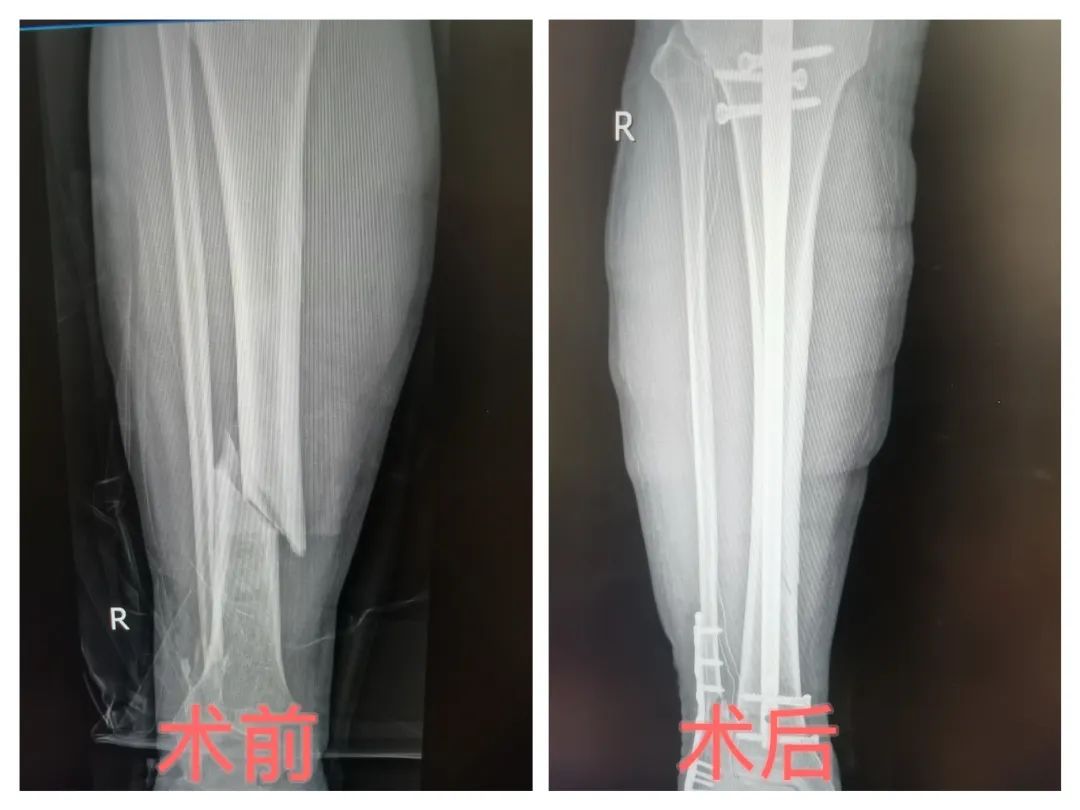

胫骨骨折怎么办?万医髌上入路胫骨髓内钉内固定微创手术,让您的康复更轻松!

传统手术带来的大切口、漫长恢复期总让人望而却步。为减轻胫骨骨折患者治疗痛苦,铜仁市万山区人民医院骨二科主任罗杨带领科室手术团队,采用“髌上入路胫骨髓内钉内固定术”的微创方式为多名胫骨骨折患者进行手术,重塑患者骨骼健康。微创手术以创新技术颠覆传统治疗模式,为患者带来创伤小、恢复快、效果优的全新康复体验!

胫骨骨折微创手术借助高清影像设备(如C型臂X光机、3D导航系统)精准定位骨折部位,通过2-3厘米微小切口,采用髓内钉固定、经皮钢板置入等先进技术复位骨折断端,无需大面积切开肌肉和软组织,就能实现骨折部位的稳定固定,为骨骼愈合创造良好条件。

5. 精准复位,效果佳:在影像设备引导下,医生能更精准地完成骨折复位与固定,确保骨骼恢复原有解剖结构,提高骨折愈合质量。